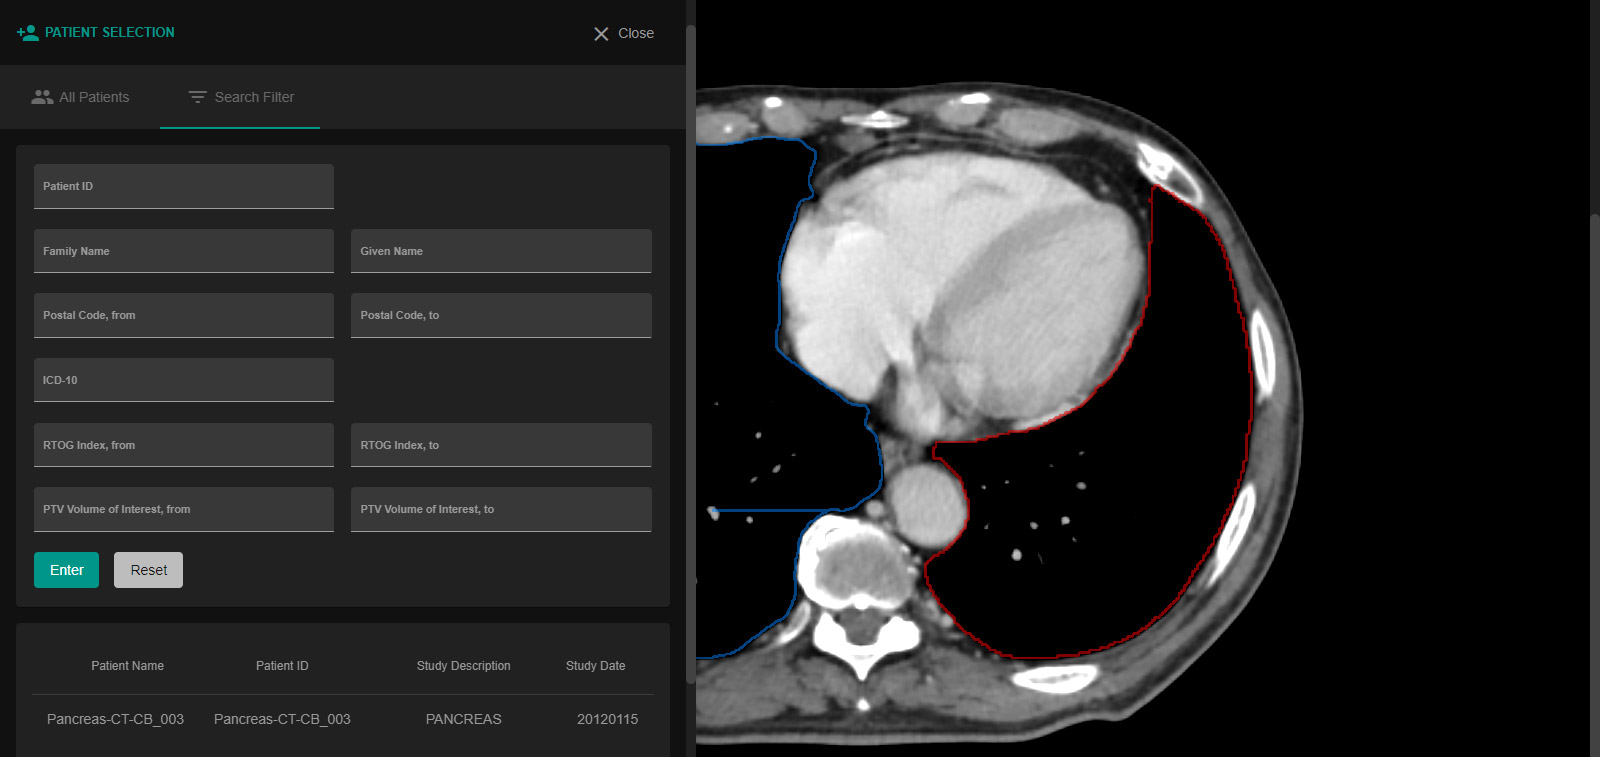

Enhance care with our medical Python Library Rt Dicom Monaco gallery of comprehensive galleries of therapeutic images. medically documenting photography, images, and pictures. designed to support medical professionals. Discover high-resolution Python Library Rt Dicom Monaco images optimized for various applications. Suitable for various applications including web design, social media, personal projects, and digital content creation All Python Library Rt Dicom Monaco images are available in high resolution with professional-grade quality, optimized for both digital and print applications, and include comprehensive metadata for easy organization and usage. Discover the perfect Python Library Rt Dicom Monaco images to enhance your visual communication needs. Our Python Library Rt Dicom Monaco database continuously expands with fresh, relevant content from skilled photographers. Instant download capabilities enable immediate access to chosen Python Library Rt Dicom Monaco images. Diverse style options within the Python Library Rt Dicom Monaco collection suit various aesthetic preferences. The Python Library Rt Dicom Monaco archive serves professionals, educators, and creatives across diverse industries. Regular updates keep the Python Library Rt Dicom Monaco collection current with contemporary trends and styles. Comprehensive tagging systems facilitate quick discovery of relevant Python Library Rt Dicom Monaco content. Time-saving browsing features help users locate ideal Python Library Rt Dicom Monaco images quickly.